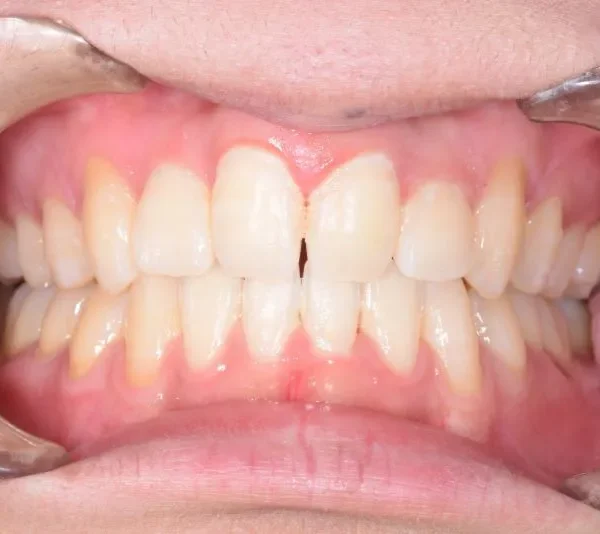

• 治療終了後

治療終了後

ガタガタ・八重歯を主訴に来院された患者様です。

治療回数42回、3年1ヶ月の治療期間で矯正治療を終了しました。

主訴が改善され、ご満足頂きました。